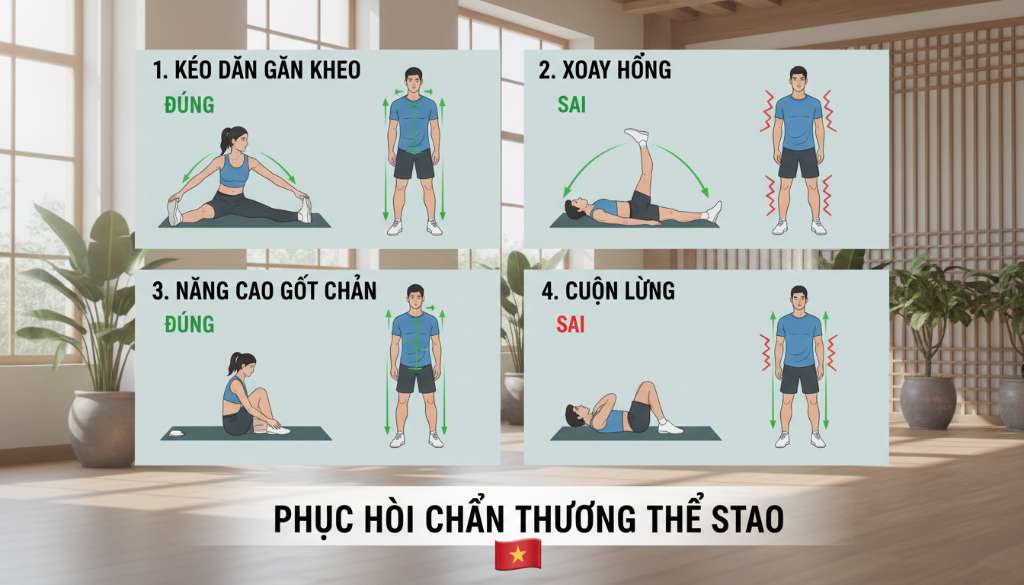

Phác đồ phục hồi và bài tập điều trị hiệu quả tại nhà

Thay vì nghỉ ngơi hoàn toàn và chườm đá theo phương pháp RICE cũ, y học thể thao hiện đại năm 2024 ưu tiên phác đồ PEACE & LOVE. Chúng tôi khuyến khích bạn thực hiện "nghỉ ngơi tương đối", nghĩa là vẫn vận động nhẹ nhàng dưới ngưỡng đau (dưới 3/10 trên thang điểm VAS).

Chìa khóa để điều trị dứt điểm PFPS không nằm ở thuốc giảm đau mà nằm ở việc tái thiết lập sự cân bằng cơ bắp. Bạn cần tập trung vào các bài tập làm khỏe cơ hông và cơ đùi trước. Dưới đây là lịch tập bổ trợ gợi ý từ chuyên gia của Vietnam's Best Marathon: